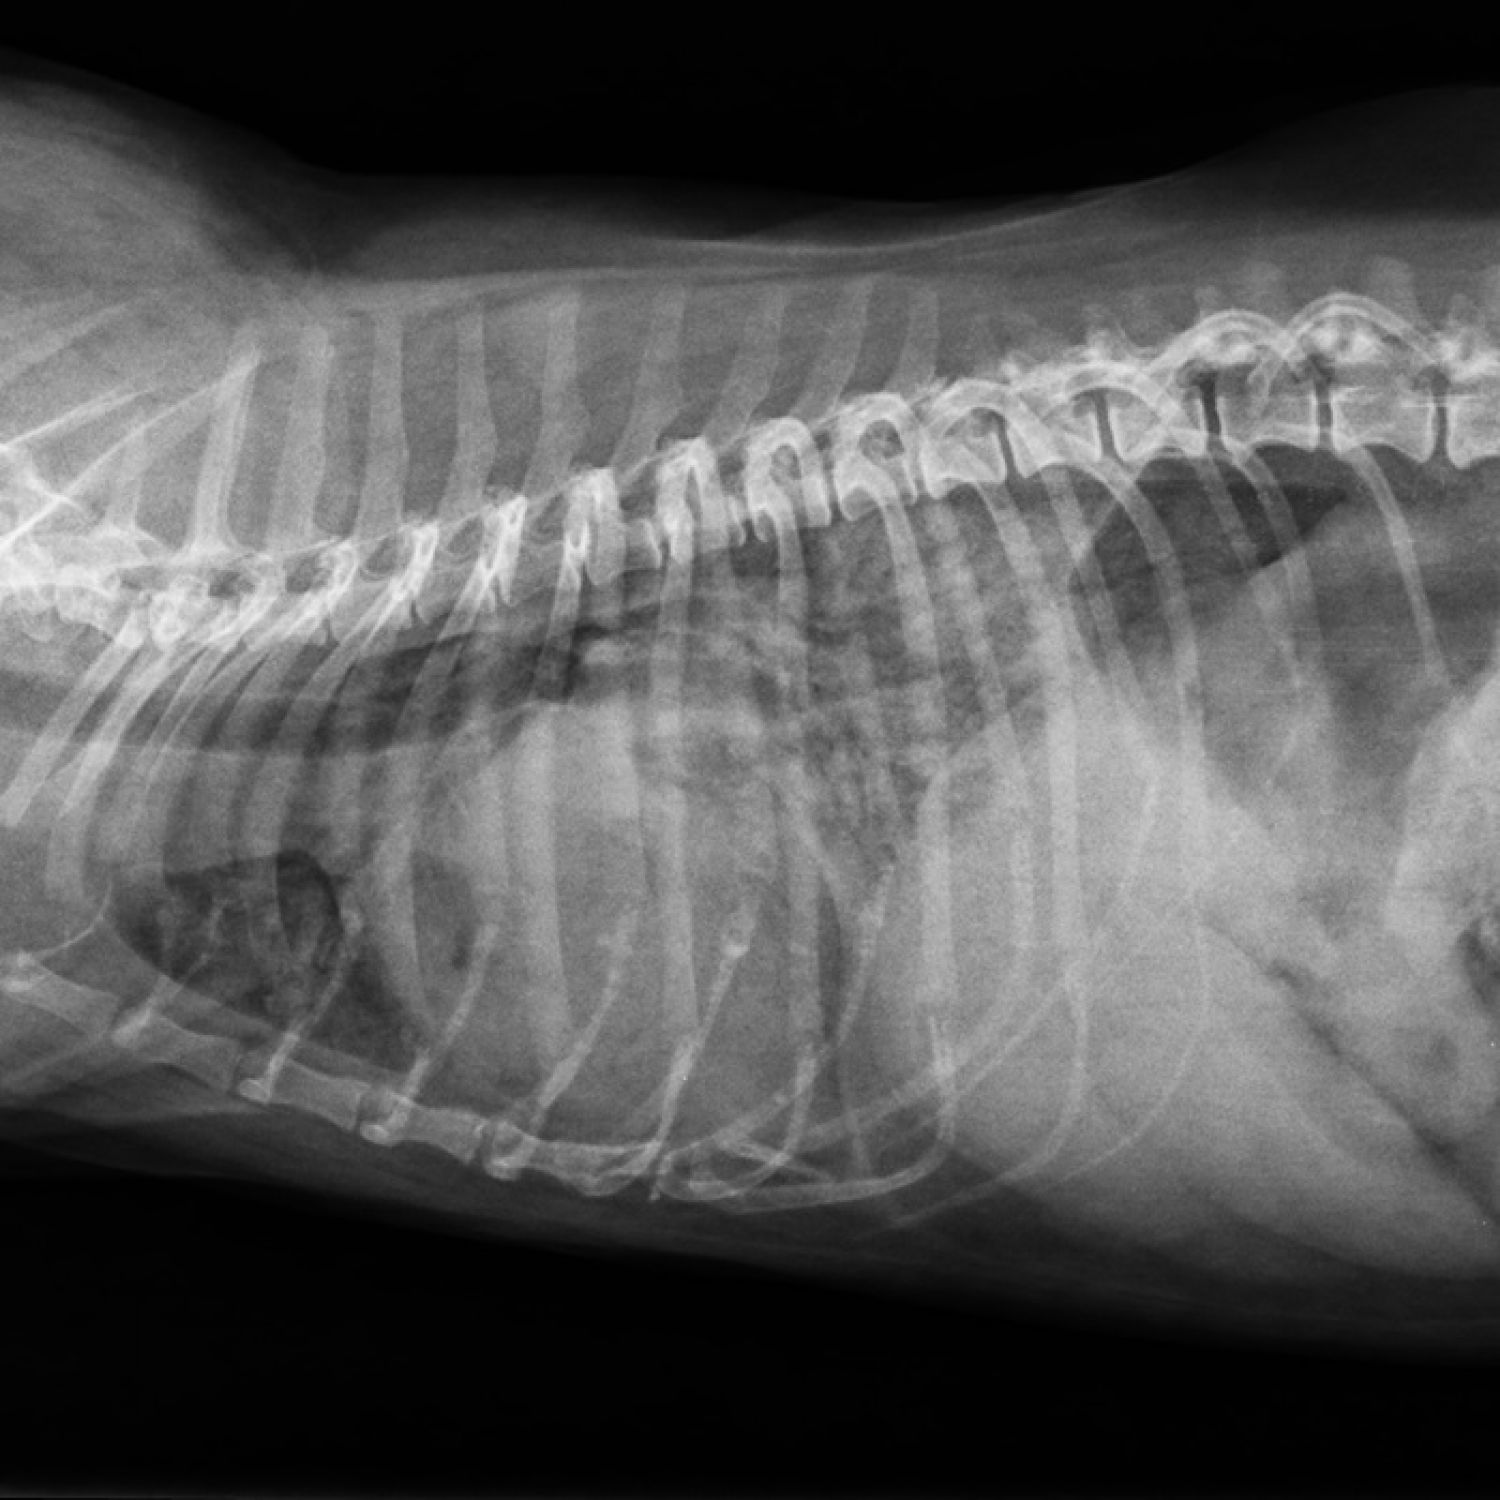

Edem pulmonar posibil cardiogen

Cord globulos, edem pulmonar posibil cardiogen, silueta splenica marita, cu margini rotunjite, aerocolie gastrica pe fond de dispnee severa